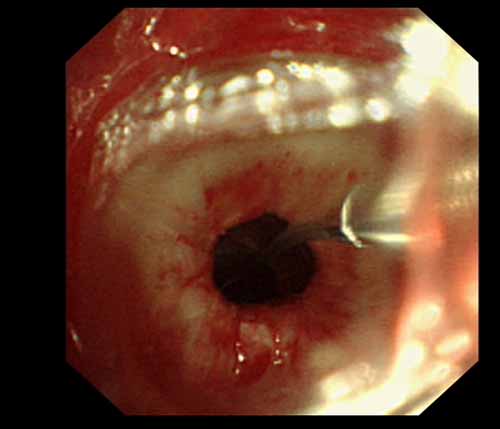

患者李某某,女,45歲,因氣管插管咳嗽、喘憋10天入院。頸部CT檢查示聲門下約20mm處氣管明顯狹窄,狹窄段長(zhǎng)約26mm,最窄處直徑約4.4mm。支氣管鏡檢查見(jiàn)聲門下約2cm氣管呈漏斗狀縮窄,直徑約4-5mm,支氣管鏡無(wú)法通過(guò)。經(jīng)科室討論,決定行電子支氣管鏡下氣管球囊擴(kuò)張治療。與患者及家屬充分溝通并經(jīng)三方見(jiàn)證談話簽署知情同意書(shū)后,在患者持續(xù)吸氧、局麻下,科主任于世倫主任醫(yī)師帶領(lǐng)治療小組為患者實(shí)行電子支氣管鏡下氣管球囊擴(kuò)張術(shù)。手術(shù)過(guò)程順利,出血量很少,術(shù)后患者呼吸困難癥狀即可明顯緩解。10天后行二次擴(kuò)張,患者日常活動(dòng)無(wú)明顯喘憋,二次術(shù)后5天出院。

術(shù)中球囊擴(kuò)張